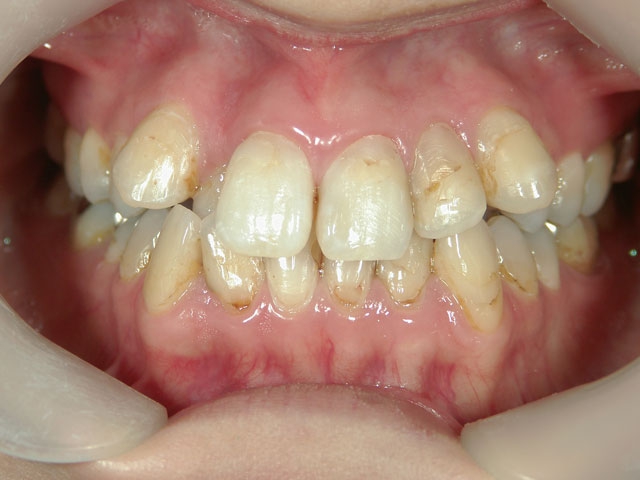

矯正歯科 治療前矯正歯科 治療前

28歳女性 浜松市中区在住

治療期間2年6ヶ月

矯正歯科 治療前 外科手術併用(コルチコトミー)、非抜歯